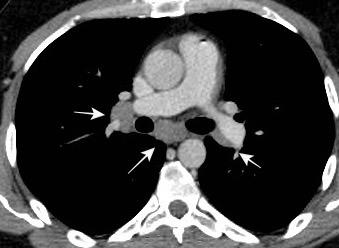

Triada de Garland

Ganglios paratraqueales derechos e hiliares bilaterales

95% de pacientes tienen ganglios hiliares bilaterales aislados o con afectación mediastínica (espec. paratraqueal derecho).

Criado E et al. Pulmonary sarcoidosis: typical and atypical manifestations at high-resolution CT with pathologic correlation. Radiographics. 2010